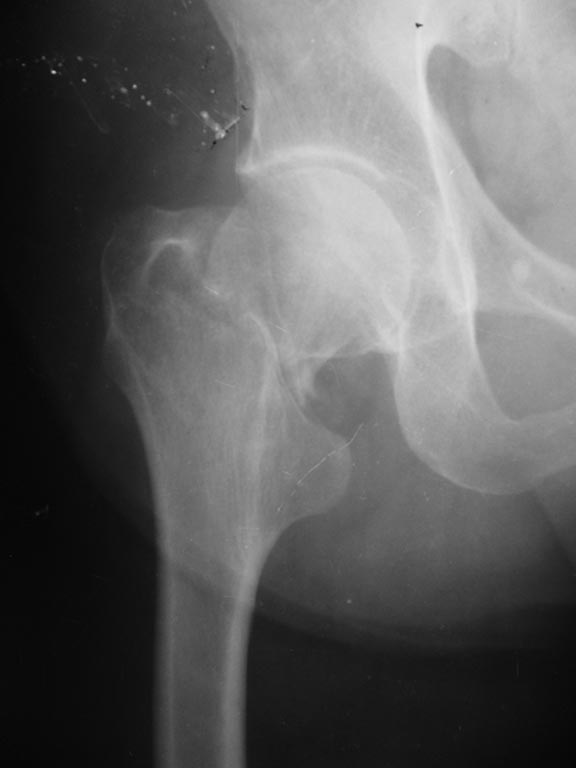

Уважаемые коллеги! Поступил пациент 60 лет с переломом шейки бедра спустя 6 часов - упал на улице. Был в алкогольном опьянении, сейчас нормальный. Тяжелой сопутствующей патологии нет.

Здесь даже намека нет на вколоченный перелом.

Это Garden III-IV, так что у пациента мужского пола в этом возрасте надежнее эндопротезирование. Если по каким-то причинам этот вариант недоступен, то остеосинтез лучше сделать хотя бы не винтами, а каким-то из fixed angle implants - PFN, DHS, Targon FN...

Не похоже на вколоченный перелом. Аксиальная проекция - красивая "художественная" иллюзия - хорошая.